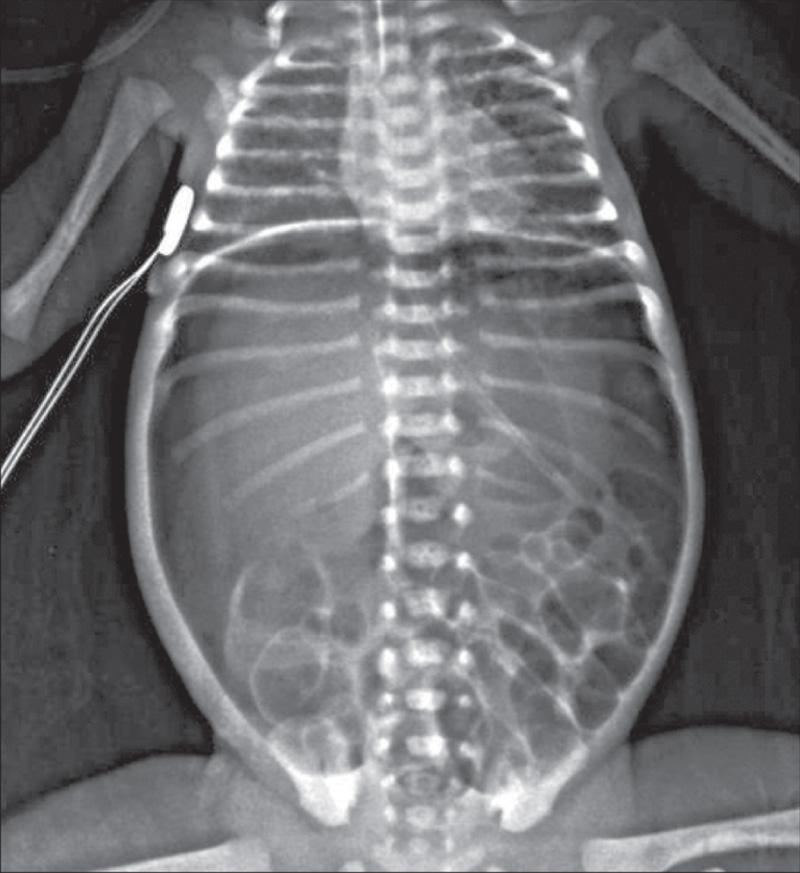

The differential diagnosis involves other causes of intestinal obstruction, including intestinal pseudoobstruction, and other causes of pancreatic insufficiency (see Chapter 377 ). Prenatal diagnosis is readily achieved by ultrasound with identification of enlarged bowel loops or a mass with distention of the proximal small bowel. Clinically the diagnosis can be made with a history of CF in a sibling, by palpation of doughy or cordlike masses of intestines through the abdominal wall, and from the radiographic appearance. Plain radiographs reveal small bowel obstruction. Air-fluid levels may not be apparent because of the thickened meconium.

In contrast to the generally evenly distended intestinal loops above an atresia, the loops may vary in width and are not as evenly filled with gas. At points of heaviest meconium concentration, the infiltrated gas may create a bubbly, granular appearance ( Figs. 123.2 and 123.3 ).

Fig. 123.2, Meconium ileus.

Fig. 123.3, Uncomplicated meconium ileus.